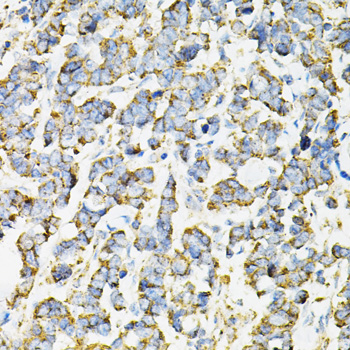

Immunohistochemistry of paraffin-embedded human lung cancer using ADSS at dilution of 1:100 (40x lens).

Immunohistochemistry of paraffin-embedded human esophageal cancer using ADSS at dilution of 1:100 (40x lens).